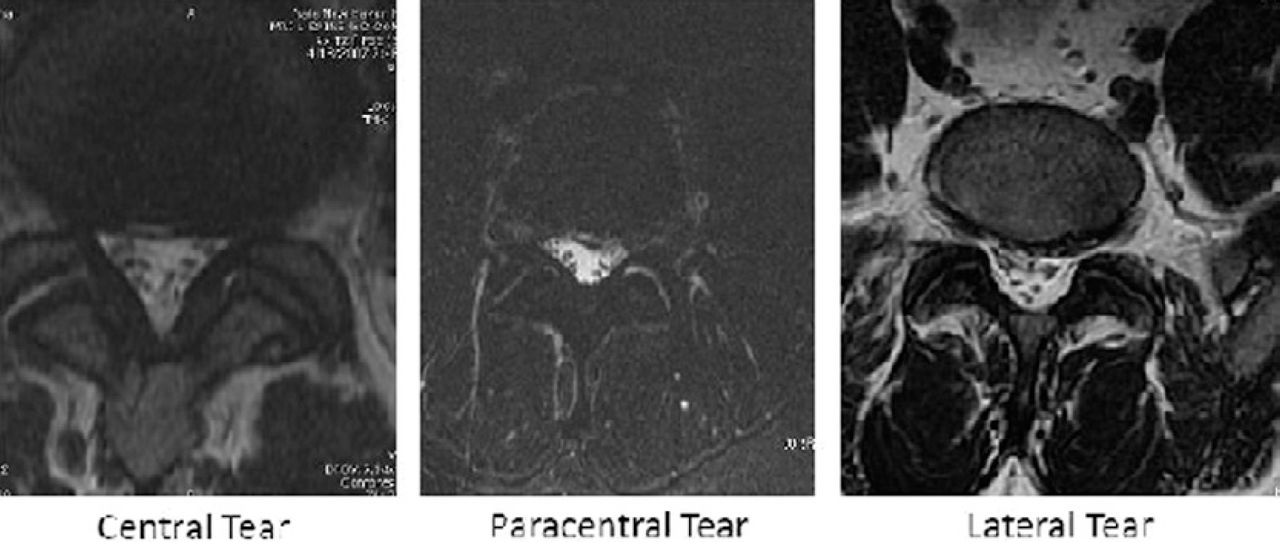

Fig. 14.3, [MRI of annular tear]. Musculoskeletal Diseases 20212024 Annular Tear Lumbar Disc Treatment Annular tear treatment in clearwater, fl what is an annular tear? Find out the symptoms of treatment options for an annular tear of the lumbar disc, a spinal condition that requires prompt attention An annular fissure is a discogenic condition that affects the spine and can cause lower back pain. We have extensive experience in the treatment of annular tears. Annular Tear Lumbar Disc Treatment.